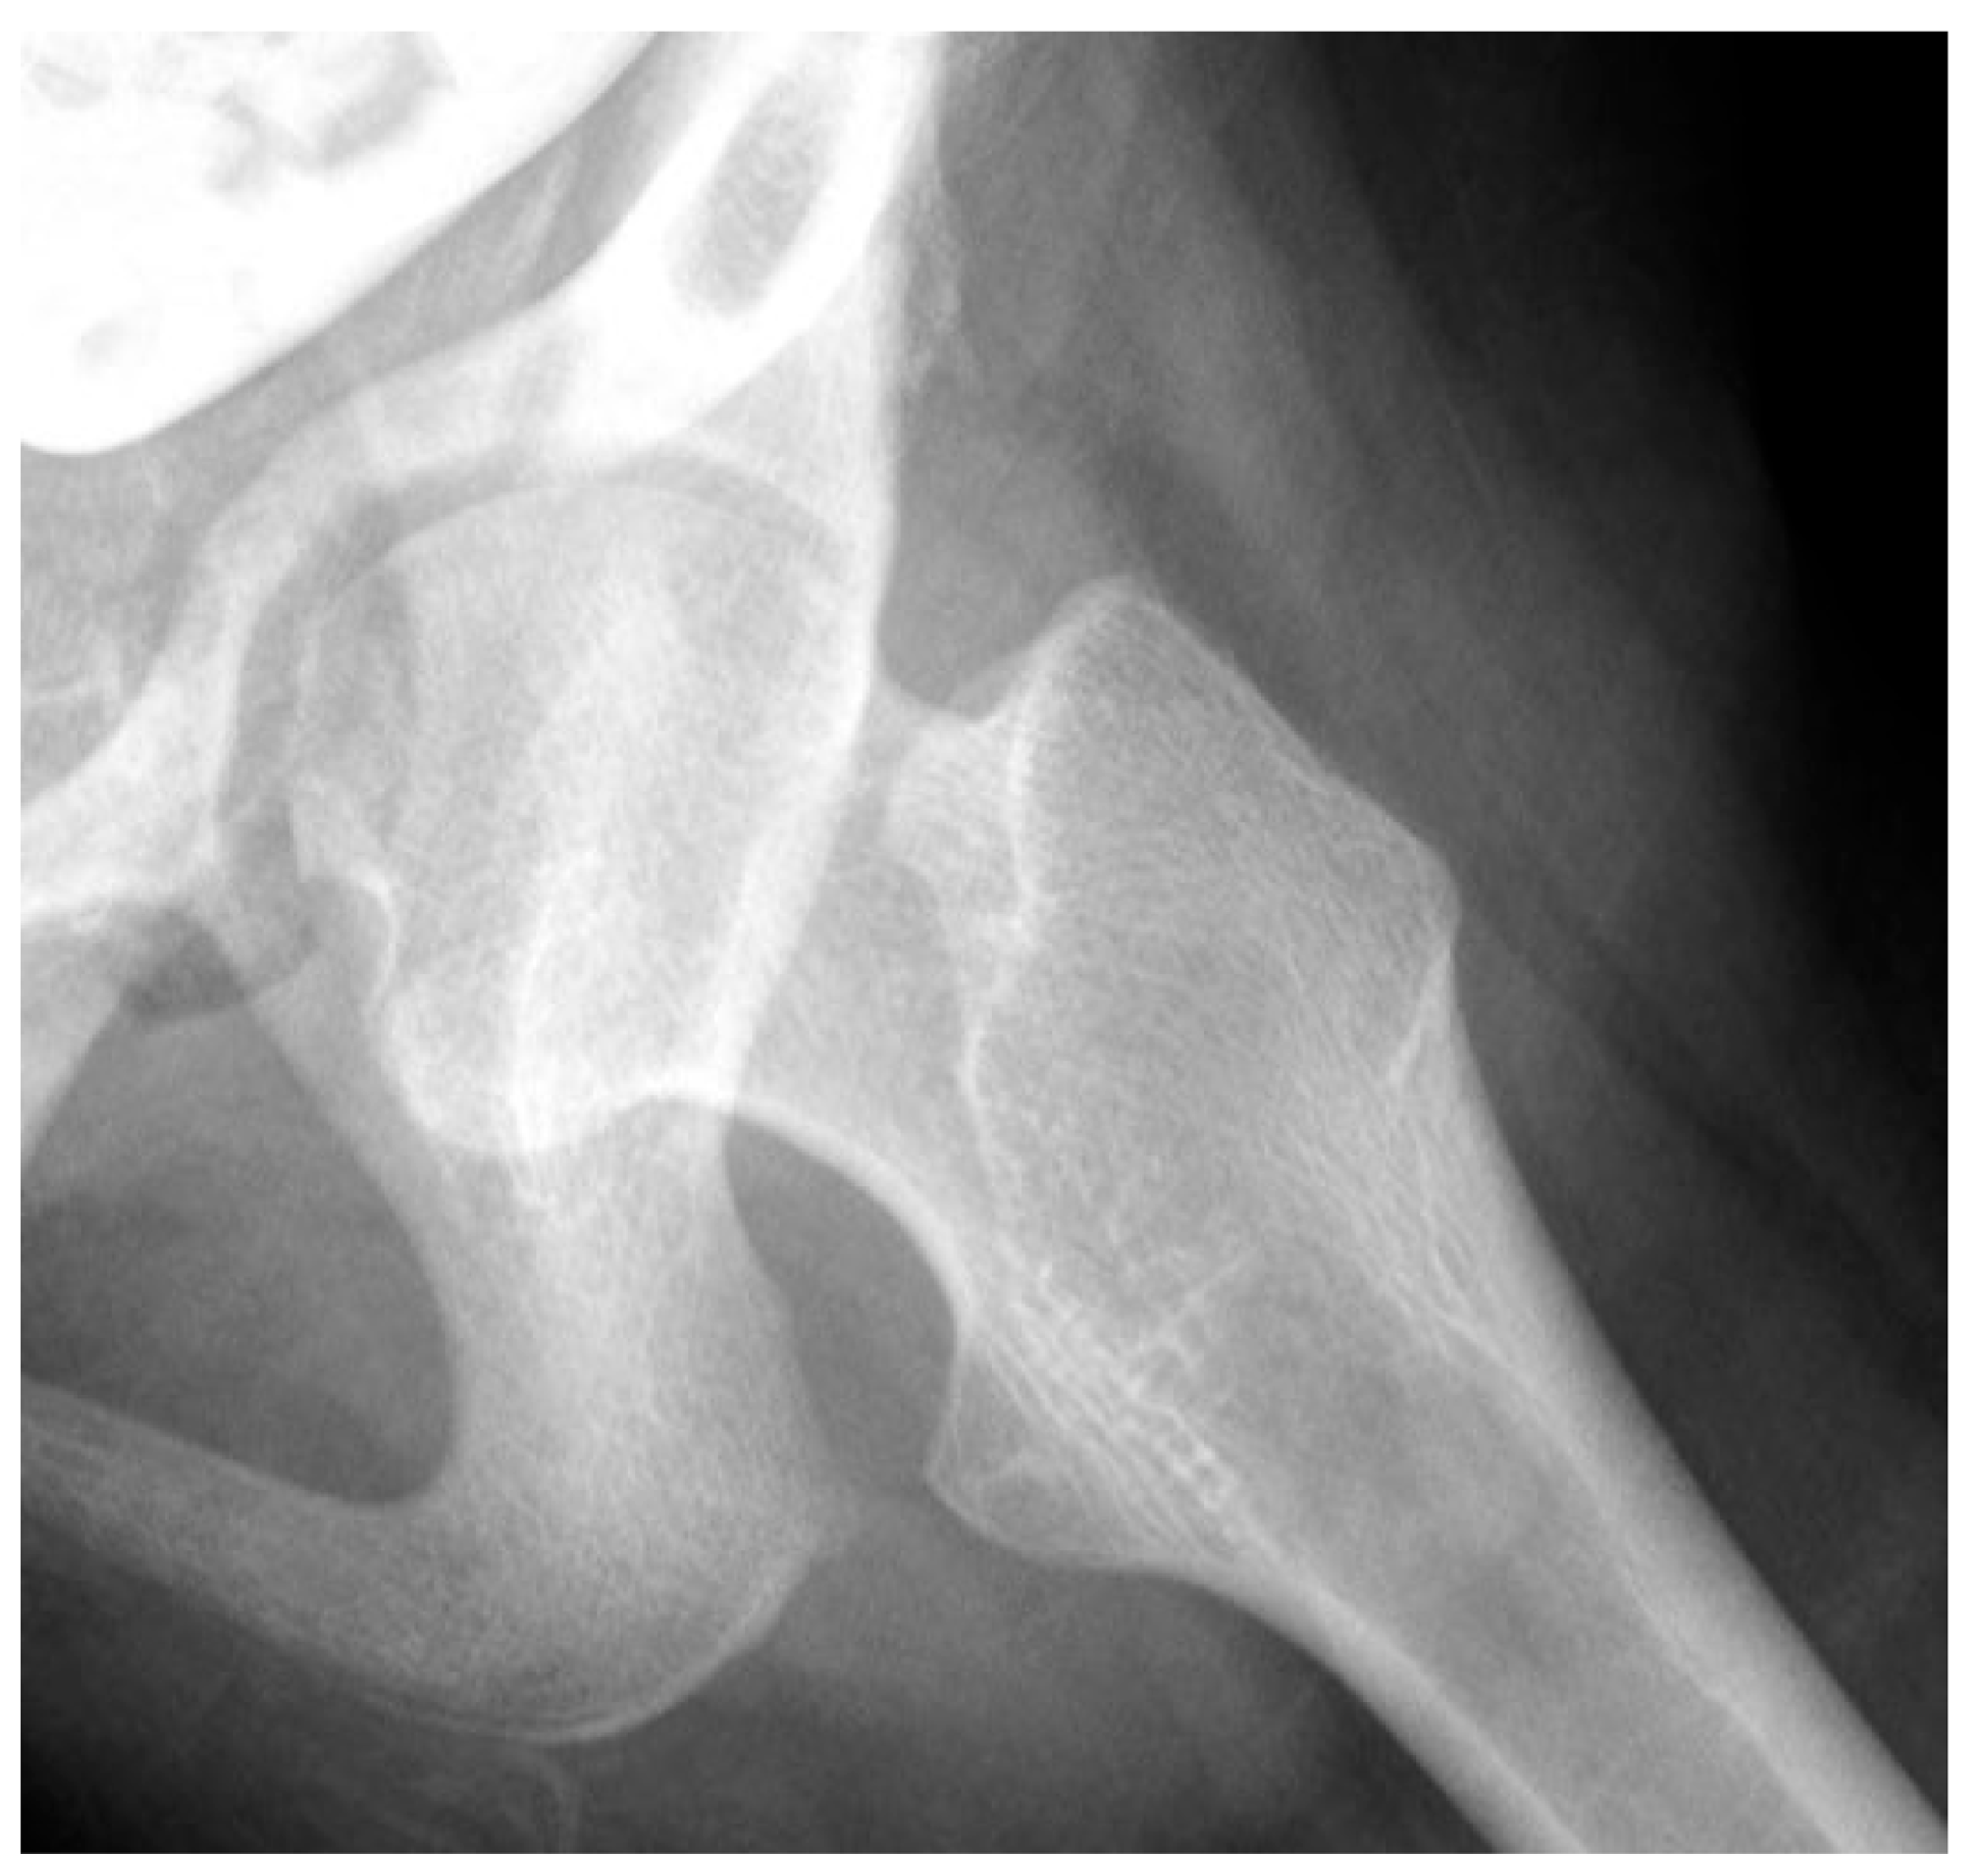

3.4. Femoral Factors Influencing Hip Pathology

3.4.1. Pathologic Role of Femoral Anteversion

3.4.2. Pathologic Role of Coxa Valga and the Impact of its Correction on Spastic Hips